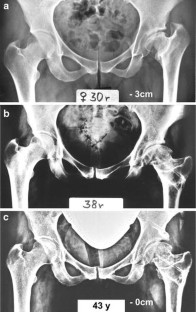

Fig. 2